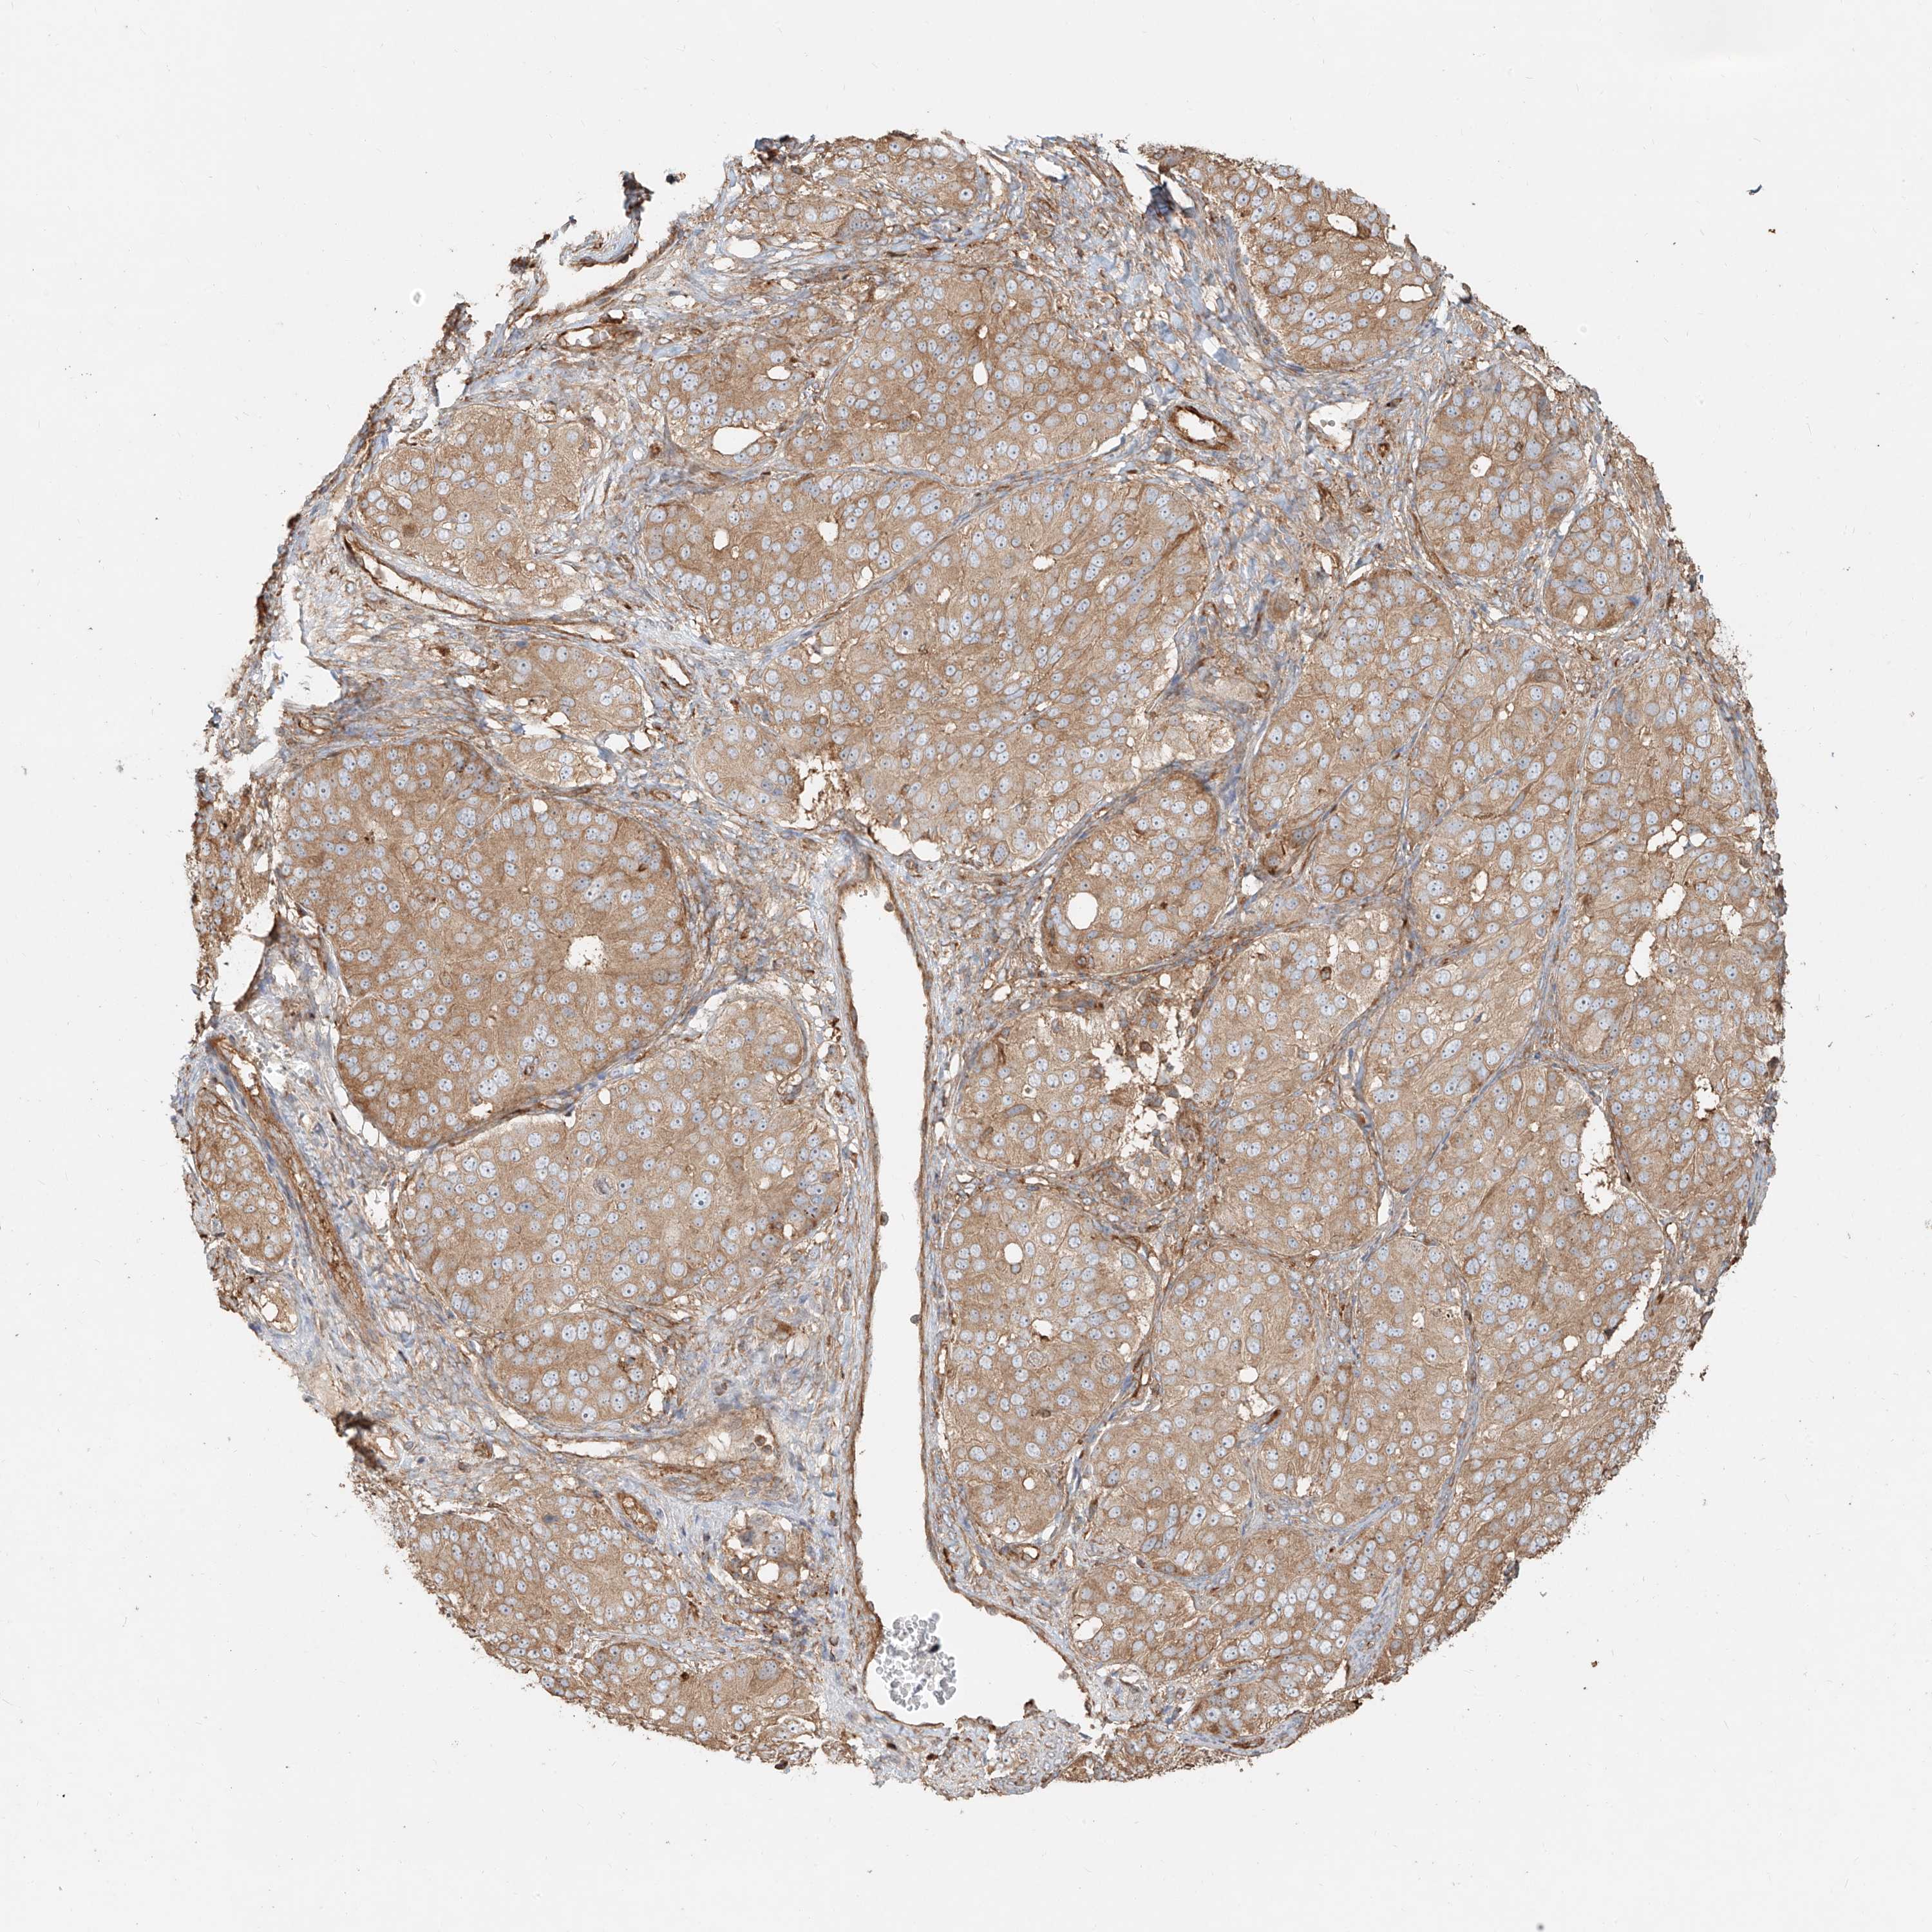

OVARIAN CANCER - Protein expressioni

A mouse-over function shows sample information and annotation data. Click on an image to view it in a full screen mode. Samples can be filtered based on level of antibody staining by selecting one or several of the following categories: high, medium, low and not detected. The assay and annotation is described here.

Note that samples used for immunohistochemistry by the Human Protein Atlas do not correspond to samples in the TCGA dataset.

Antibody stainingi

Antibody staining in the annotated cell types in the current human tissue is reported as not detected, low, medium, or high, based on conventional immunohistochemistry profiling in selected tissues. This score is based on the combination of the staining intensity and fraction of stained cells.

Each image is clickable and will lead to virtual microscopy that enables deeper exploration of all samples and also displays staining intensity scores, fraction scores and subcellular localization as well as patient and tissue information for each sample.

Antibody HPA031410

Staining

High

Medium

Low

Not detected

Intensity

Strong

Moderate

Weak

Negative

Quantity

>75%

75%-25%

<25%

None

Location

Nuclear

Cytoplasmic/membranous

Cytoplasmic/membranous,nuclear

Cystadenocarcinoma, serous, NOS

Carcinoma, endometroid

Cystadenocarcinoma, mucinous, NOS

Carcinoma, NOS